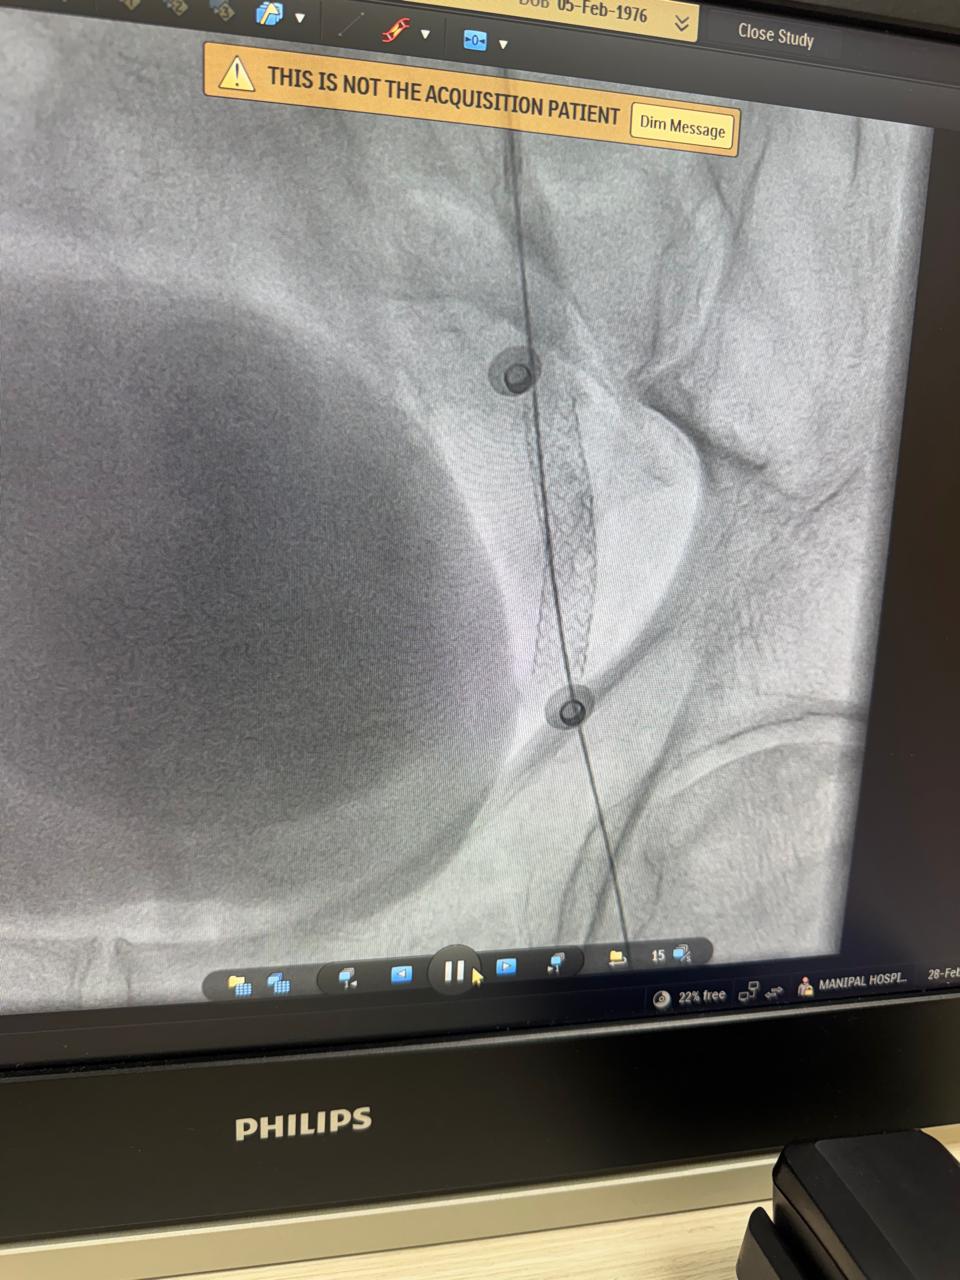

Right femoropopliteal bypass with synthetic graft+graft to posterior tibial artery vein bypass